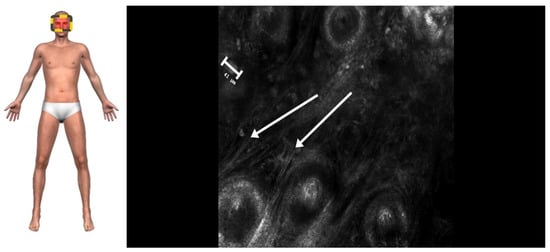

2. Case Presentation

3.2. Advantages of RCM in Periocular Diagnosis

3.3. RCM as an Emerging Diagnostic Tool